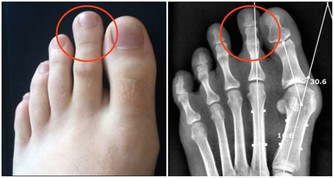

4、腳趾甲變厚

腳趾甲變厚,最有可能是灰指甲在作怪。

灰指甲又稱甲癬,是由真菌傳染到趾甲而引起的,且多發生在糖尿病患者、有循環問題和免疫問題的人身上。

建議:

甲癬患者一般很難發覺患有此病,所以平時要做好預防工作,注重局部衛生,保持腳部乾燥通氣;一旦發現,及時治療。